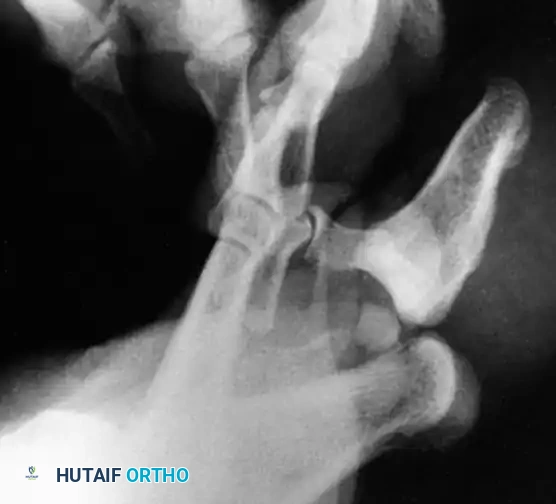

FIRST METATARSOPHALANGEAL (MTP) JOINT DISLOCATIONS

Pathoanatomy and Biomechanics

Dislocation of the first metatarsophalangeal joint is a rare but highly complex injury. The mechanism is extreme hyperextension of the great toe, which forces the proximal phalanx to displace onto the dorsum of the first metatarsal head and neck.

This displacement creates a formidable anatomical "noose" around the metatarsal head, making closed reduction exceptionally difficult. The metatarsal head becomes tightly trapped by the following structures:

* Medially: The medial head of the flexor hallucis brevis (FHB) and the abductor hallucis tendon.

* Laterally: The lateral head of the FHB and the adductor hallucis tendon.

* Dorsally: The displaced plantar plate and the deep transverse metatarsal ligament.

* Plantarward: The tight plantar aponeurosis prevents the metatarsal head from dropping back into position.

* Note: The flexor hallucis longus (FHL) tendon typically subluxates lateral to the metatarsal head.

Fig. 86-53 Dorsomedial dislocation of fi rst metatarsophalangeal joint. A, Dislocation could not be reduced by closed means. B, After open reduction, joint was stable.